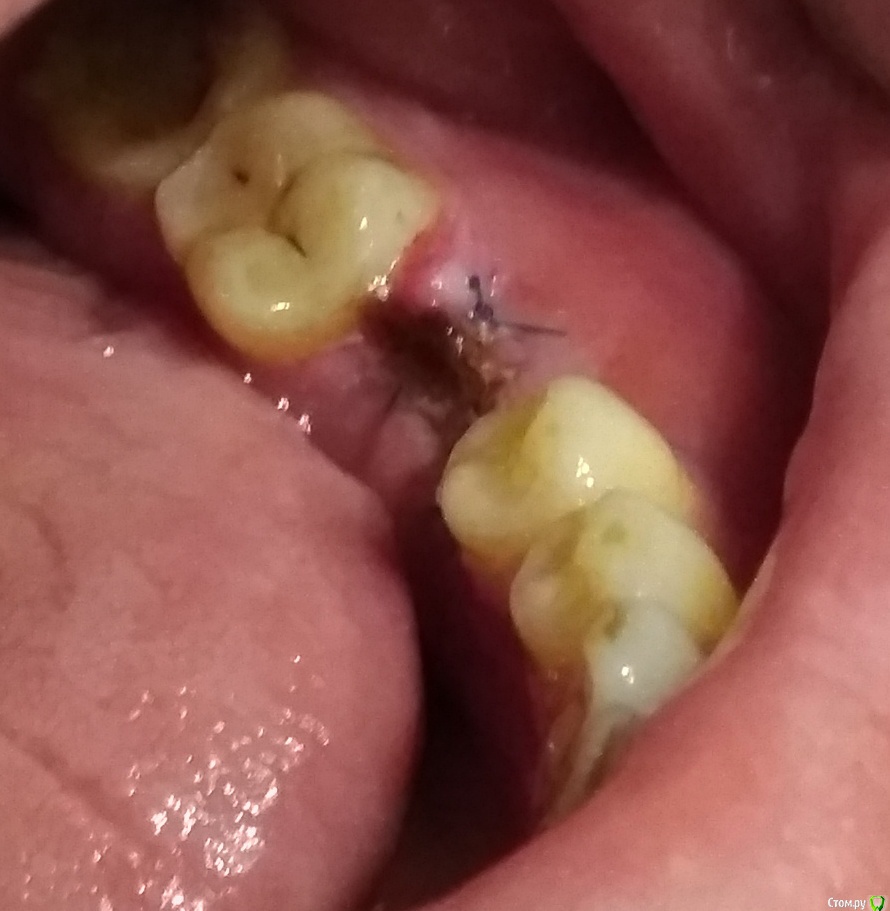

Устала Опубликовано 26 апреля, 2018 Автор Поделиться Опубликовано 26 апреля, 2018 Уважаемы доктора! Вот!Ситуация во рту - это сегодня после очередного упражнения доктора в кройке и шитье.Может уже бежать к другому, что скажите? Ссылка на комментарий

Устала Опубликовано 26 апреля, 2018 Автор Поделиться Опубликовано 26 апреля, 2018 (изменено) Вот ещё. Тут может получше.Сегодня доктор хотел выкрутить формирователь, но не смог. Достал другой формирователь, наверное, хотел поменять его, но вот не случилось. Отправил так. Изменено 26 апреля, 2018 пользователем Устала Ссылка на комментарий